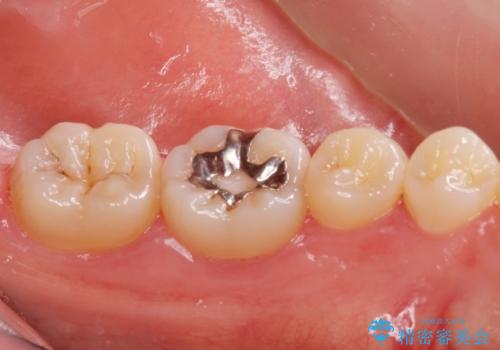

- 銀の詰め物のやりかえを希望された患者様です。

白い歯にしたいとの事だったのでセラミックインレー(e-maxインレー)にて治療しました。

- e-maxインレー 7.7万円 費用は治療当時の料金となります